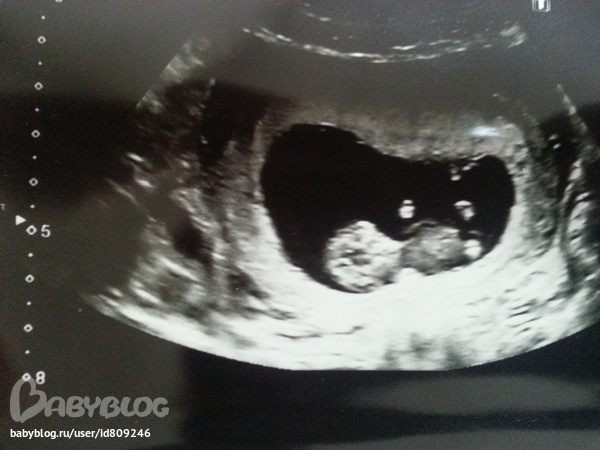

На УЗИ нам сказали, что все в порядке)

ТВП 0,9мм

КТР 37,9мм

срок 10недель 5 дней))

Папа нас забрал из поликлинники и отвез на работу) Правда пока отказывается со мной топать на УЗИ, довольствуется снимками)) Личико кроха решил не показывать) отвернулся)))